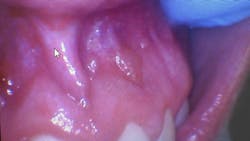

Clinical dental case: Asymptomatic fluid-filled lesions in the vestibular mucosa (nos. 7–10)

Patient presentation: A 17-year-old male patient presented at the initial dental appointment with the following:

Chief complaint: None. The lesions were discovered during a routine oral examination.

Clinical findings:

- Seven asymptomatic, fluid-filled lesions

- Lesions ranged in size from 2 mm to 5 mm

- Lesions similar in color to the surrounding mucosa

- Location: vestibular mucosa, in the region of teeth nos. 7–10

Follow-up appointment: Only three of the original lesions remained.

The presentation of multiple, asymptomatic, fluid-filled lesions on the vestibular mucosa, with a color similar to the surrounding tissue, further supports the likelihood of a mucocele or a mucous retention cyst. The spontaneous resolution of some lesions further strengthens this hypothesis.